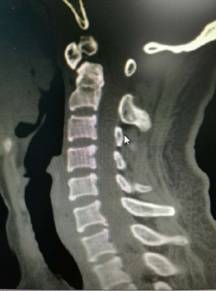

1、手术高水平:能完成各种复杂的颈椎病、腰椎间盘突出症、腰椎管狭窄症、腰椎滑脱、脊柱畸形的手术治疗和上颈椎手术、脊柱肿瘤、胸椎置换等高难度手术,技术理念和手术方法先进,积累了丰富而独特的经验,手术技术达到淮海经济区先进水平。

2、脊柱手术微创化理念:采用椎间孔镜等脊柱微创手段实施各种脊柱微创手术。治愈了大量的腰间盘突出症、腰椎管狭窄症、颈椎病患者。采用PVP、PKP术治愈了大量高龄脊柱压缩性骨折患者,近年来累计完成4000例该微创手术。60%的脊柱病人可以进行微创手术,具有创伤小、效果好、安全性高、恢复快、术后不需长期卧床等特点。微创手术保持极高的优良率与可靠性。脊柱微创技术居于淮海经济区先进水平。我院在淮海经济区率先开展颈椎微创手术。

颈椎前路减压融合内固定术治疗脊髓型颈椎病

优点:直接减压,彻底解决突出问题,稳定。

颈椎后开门Arch钛板固定术治疗颈椎后纵韧带骨化症

优点:减压范围广,疗效缺切,保留颈椎的活动度。

寰枢椎固定融合术治疗颅底凹陷、齿状突骨折等

特点:手术风险高。